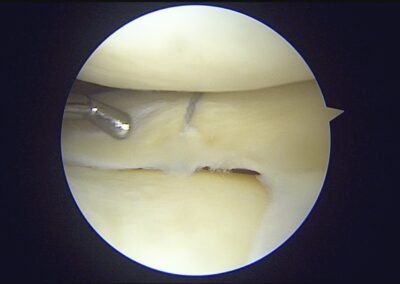

GalleryShoulder rotator cuff repair Meniscus root repair Meniscus repair Bankart repair for recurrent shoulder dislocation ACL reconstruction Machines Instruments